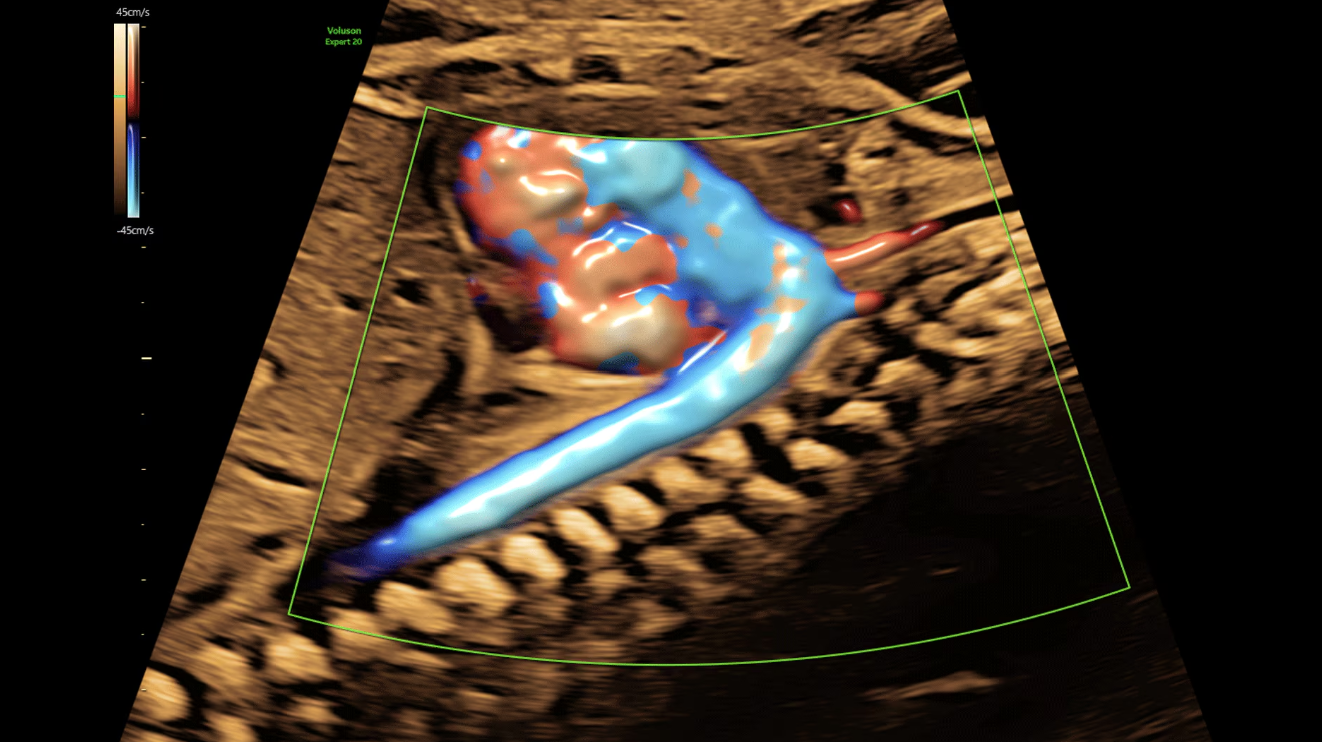

Дуга аорты, показанная с помощью Radianflow у плода на 26 неделе беременности

Пуповина и плацента с помощью Slowflow3D и HDlive